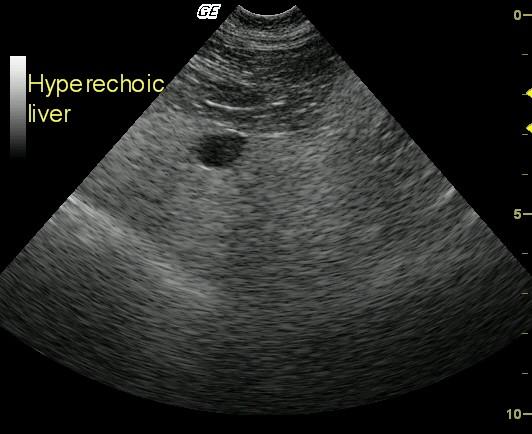

Longitudinal view of the midliver, gallbladder (11 o’clock position), and falciform fat (top) reveals markedly diffuse hyperechoic parenchyma compared with the falciform fat.

These findings are consistent with an infiltrative process. US-guided FNA revealed plasma cell neoplasia and moderate hepatic lipidosis.

Owing to moderate PT and aPTT elevations, as well as the poor clinical status of the patient, US-guided FNA rather than biopsy was performed. The cytology revealed plasma cell neoplasia and moderate hepatic lipidosis.